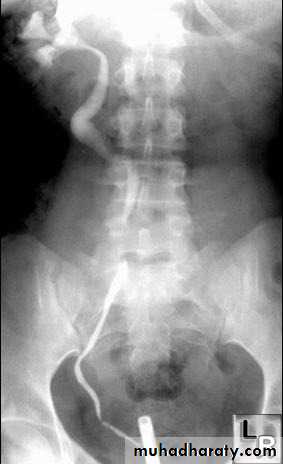

5. Ureterocele : congenital variant with dilatation of the distal ureters as it enters through the bladder wall. It produce typical appearance of cobra head which is usually of little clinical significance